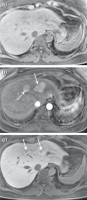

Abbildung 5a-c: KM-Anfärbeverhalten des HCC. (a) In dem T1-gewichteten MRT-Bild zeigt sich in der arteriellen Phase nach KM-Gabe eine ca. 3 cm große, typischerweise hypervaskularisierte Raumforderung im rechten Leberlappen subkapsulär (Pfeil). (b) In dem T1-gewichteten Bild nach KM-Gabe zeigt die ca. 3 cm große Raumforderung im rechten Leberlappen subkapsulär (Pfeil) ein inhomogenes Wash-out. Die Kapsel zeigt eine KM-Aufnahme (kleiner Pfeil). (c) 20 Minuten nach Gabe von Gadoxetat zeigt die ca. 3 cm große Raumforderung im rechten Leberlappen subkapsulär (Pfeil) ebenfalls ein inhomogenes Wash-out (Pfeil), die Kapsel weist auch ein KM-Auswaschen auf (kleiner Pfeil). Die Darstellung des Ausmaßes der Leberzirrhose mit zahlreichen Regeneratknoten, fibrotischen Septen, sowie der Zeichen der portalen Hypertension mit Splenomegalie und Ösophagusvarizen hilft, eine angemessene Therapieentscheidung zu treffen.